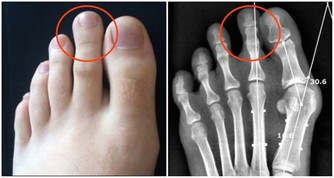

結腸腫瘤會釋放出特殊的化學物質,影響新血管的形成;

隨著腫瘤的生長,還會導致腸道內壁的血管破裂,引起內出血。

內出血不僅會導致大量紅細胞流失,還有可能造成缺鐵。

這是因為破裂的血管會誘發炎症,而炎症所產生的免疫細胞會吸附血液中的鐵。

隨著炎症的擴散,患者體內的鐵元素含量會逐漸減少,從而誘發缺鐵性貧血。